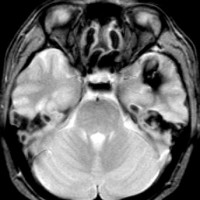

2度の延髄内出血を生じた海綿状血管腫です。でも初回の出血からすでに27年間がたちます。症状も回復して麻痺もなくていまは社会生活に困ることはありません。脳幹部の海綿状血管腫の中には1ヶ月に何回もひどい出血を繰り返すのもあるのですが,この例のように30年近い間に軽い出血が2回だけというのもあります。残念ながら正確にこれを予測することはできません。この患者さんの海綿状血管腫は手術で摘出すれば麻痺などの合併症の可能性があるのでしません。